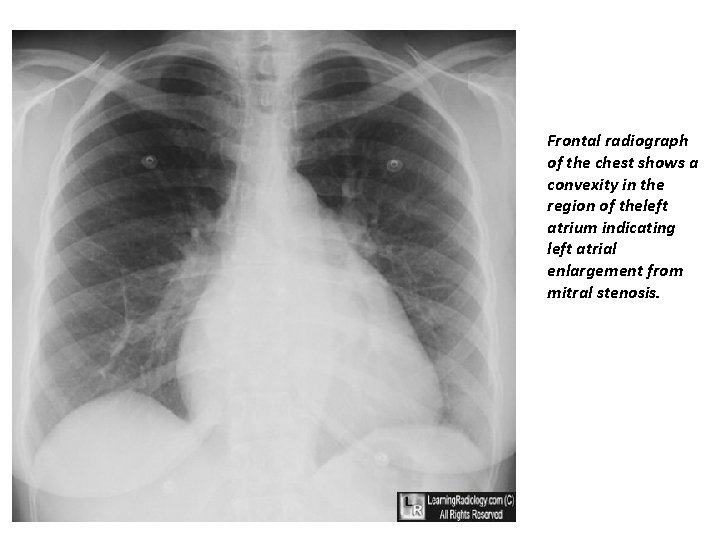

Frontal radiograph of the chest shows a convexity in the region of theleft atrium indicating left atrial enlargement from mitral stenosis.

Investigations –X-ray • Small heart with an enlarged L/ atrium • Pulmonary venous hypertension • Calcified mitral valve– on penetrated or lateral view • Signs of pulmonary oedema or pulmonary hypertension JMJ 19

Diagnosis ECG Tall R-waves (V 1 -V 3) RV hypertrophy P mitrale or atrial fibrillation Imaging X-ray (chest) Enlarged LA & appendage Signs of pulmonary venous congestion Echocardiography Thickened immobile cusps Reduced valve area Enlarged LA ↓ LV diastolic filling Doppler (DEFINITIVE) Pressure gradient across mitral valve Pulmonary artery pressure Left ventricular function Cardiac catheterisation

Complications Hemoptysis, pulmonary embolism, pulmonary infection, systemic embolization; endocarditis is uncommon in pure MS. Laboratory ECG Typically shows atrial fibrillation (AF) or left atrial (LA) enlargement when sinus rhythm is present. Right-axis deviation and RV hypertrophy in the presence of pulmonary hypertension. CXR Shows LA and RV enlargement and Kerley B lines. Echocardiogram Most useful noninvasive test; shows reduced separation, calcification and thickening of valve leaflets and subvalvular apparatus, and LA enlargement. Doppler flow recordings provide estimation of transvalvular gradient, mitral valve area, and degree of pulmonary